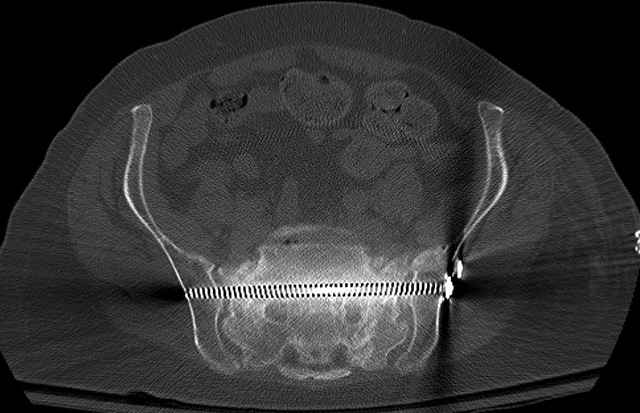

Here are a recent patient’s example slides...

54 yo Female Fell c/o Pain

Initial Films

?Instability on Exam - Limited by Pain

NonOp Initial Mgmt

3 Months After Fall

Continued Pain & Immobility

(+) Instability to Compressive Manual Exam

Pelvic CT Scan - 3 Months After Fall

Sacral Injuries

Ramus Fractures